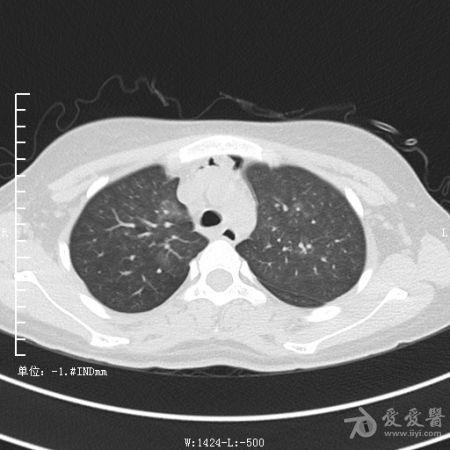

典型支气管扩张及肺水肿CT片

典型支气管扩张肺水肿